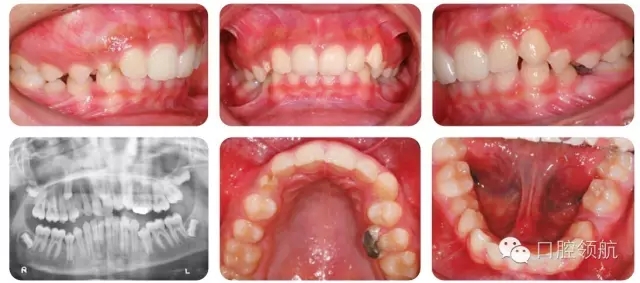

13歲的男性患者的錯(cuò)牙合畸形如圖2.42所示。

全景片情況

● 全景片確認(rèn)了該患者4顆第三磨牙均存在。

● UR3未萌出,牙冠略向遠(yuǎn)中傾斜,并接近UR4的牙根。

● UR3根尖孔未閉合。

● 下頜雙側(cè)第二前磨牙垂直阻生。

● 未萌牙的發(fā)育無(wú)病理因素存在。

● 13歲男性患者,I類關(guān)系,輕度骨性II類,均面型。

● 雙側(cè)磨牙I類關(guān)系,中線齊,雙側(cè)尖牙1/2牙尖II類關(guān)系。

● 另外伴有:

○ 1. 異位UR3。

○ 下頜第二前磨牙阻生。

○ 深覆牙合。

○ 上下牙列均存在擁擠。